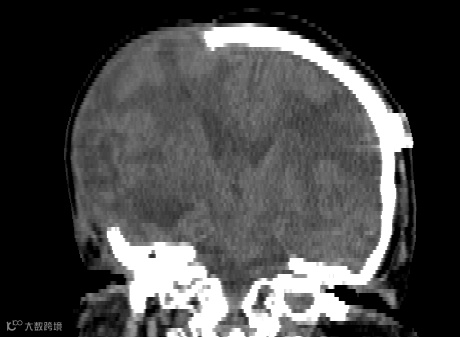

患者,女,66岁,右侧颅骨缺损

患者脑CT检查